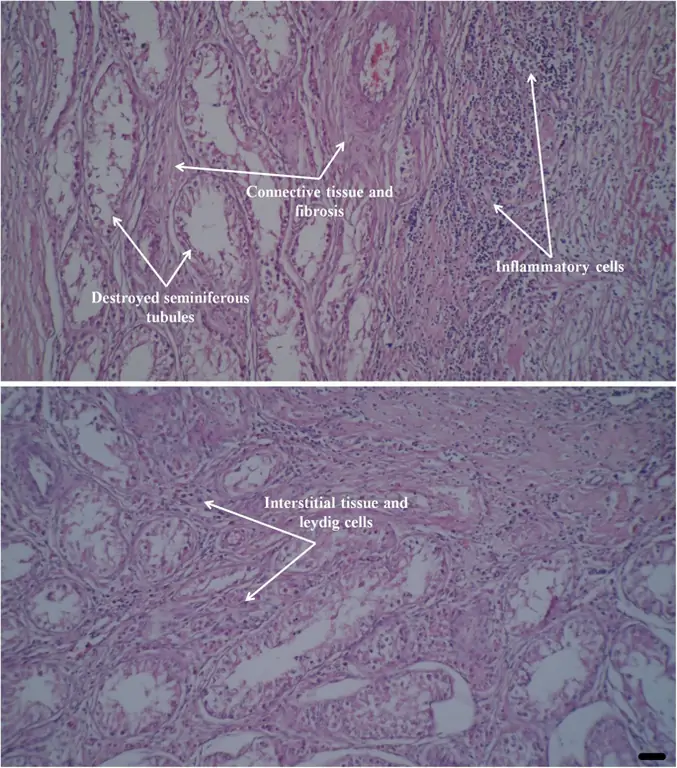

Оценка гистопатологии

Гистологическое исследование образцов выявило дегенерацию сперматогенных тканей, наличие фиброза, воспаления, кровоизлияния и наличие многоядерных сперматид. Не было никаких признаков дегенерации, некроза и фиброза в интерстициальной ткани и клетках Лейдига (рис. 4).

figure4

Гистопатологические представления о паренхиме яичка собаки представлены через 37 дней после однократного внутриклеточного введения глюконата цинка. Обнаружены дегенерация семенных канальцев и накопление воспалительных клеток. В некоторых частях присутствие соединительной ткани и фиброз очевидны через 37 дней после инъекции, в то время как клетки Лейдига и окружающая интерстициальная ткань имеют нормальный внешний вид (окрашивание H & E). Масштабная линейка составляет 13, 8 мкм